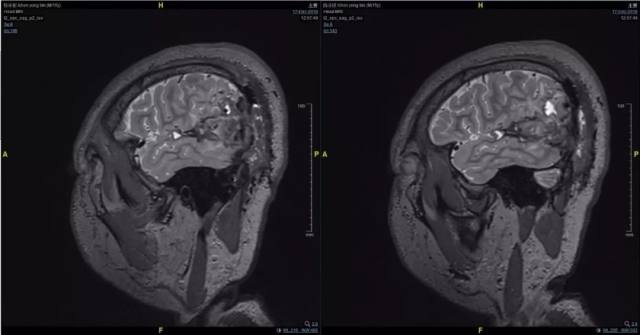

2、术前影像资料

图 3 术前 T2 矢状位:左颞顶枕血管畸形术后;混杂信号;考虑畸形残余伴出血。